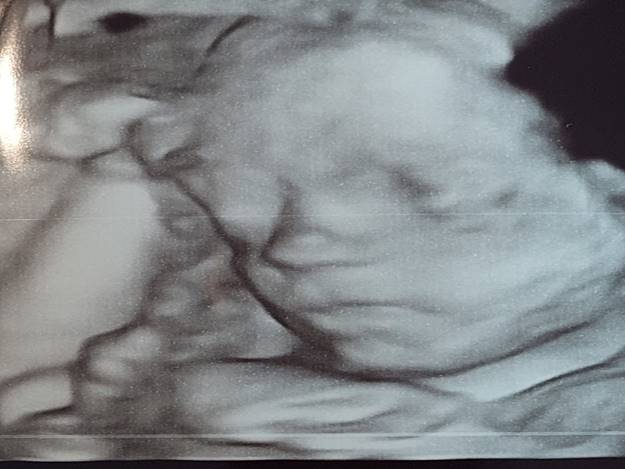

Samenwonend met Karlijn Marije DOCTER, geboren op geboren op 6 april 1988 om 7.45 uur

1. Pukje